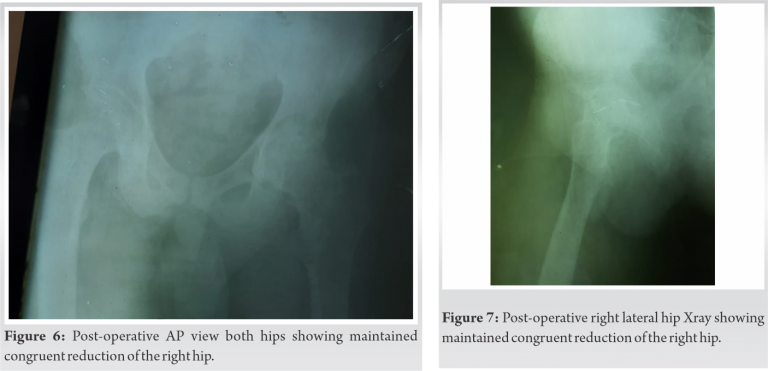

Steinman pins and sutures removed after 15 days, but the hip joint continued to be kept immobilized in Thomas Splint for 3 weeks postoperative after which gradual mobilization started (Fig. 5). Patient went discharge thereafter and returned back to his village but failed to follow-up at 6 weeks due to financial issues in addition to the restrictive travel conditions in the lockdown, now at 3 months postoperative the patient has painfree ambulation with stick support with early signs avascular necrosis (AVN) of the femoral head as seen on the X-ray and computed tomography scan (Fig. 6-8).